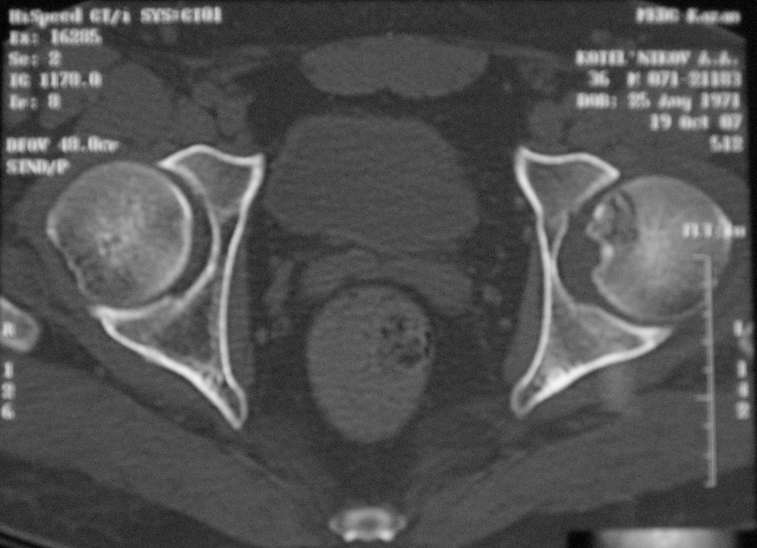

Уважаемые коллеги! Помогите с дифф. диагнозом и тактикой лечения.

Молодой человек, 37л. Начало заболевания сентябрь 2007, резкие боли в области лев.

тазобедренного сустава, повышение температуры до 39 гр., в течение недели, лабораторные

данные: лейкоцитоз со сдвигом влево. Посев крови на стерильность возбудителя не выявил. По

данным Рг, РКТ выставлен диагноз: Левосторонний коксит? Асептический некроз? Проводилось

лечение: цефсон в/в неделю, иммобилизация кокситной повязкой 1 мес. Обратился повторно 10

дней назад с жалобами на сильные боли в левом тазобедренном суставе, белая кровь

нормограмма, СОЭ 46 мм/ч. На сегодняшний день: болей не отмечает. Лаб.данные: белая кровь

нормограмма, СОЭ 30 мм/ч. Рентген и РКТ прилагаем.